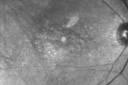

FLUORESCEIN ANGIOGRAPHY: Fluorescein angiography shows a classic bull’s eye maculopathy in each eye from the Plaquenil toxicity.